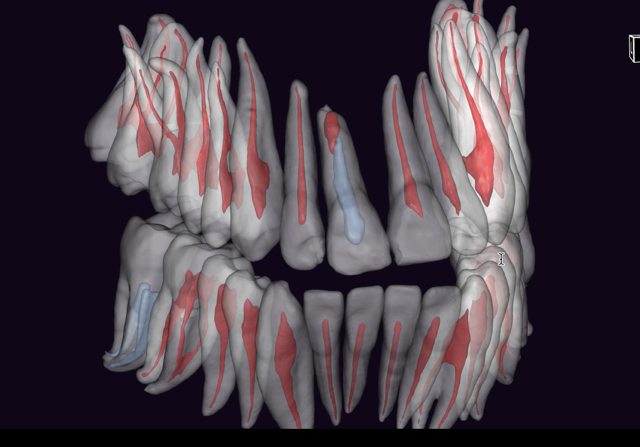

Il ritrattamento endodontico rappresenta una procedura fondamentale per la gestione di denti con fallimento della terapia endodontica primaria. Le cause principali di insuccesso possono essere legate a infezioni persistenti, fratture radicolari, o errori tecnici durante il trattamento iniziale. L’obiettivo del ritrattamento è garantire una completa decontaminazione del sistema canalare, risolvere le infezioni e favorire la guarigione dei tessuti periapicali. Questo intervento, sebbene altamente efficace, comporta sfide tecniche significative, tra cui la difficoltà nell’accesso ai canali radicolari precedentemente trattati, la rimozione di materiali di otturazione, la gestione della curvatura radicolare e la preservazione della struttura dentale residua. L’utilizzo di tecnologie avanzate, come la microscopia operativa, i laser e le apparecchiature per la localizzazione dei canali, ha migliorato notevolmente la precisione e l’efficacia di queste procedure. Durante la relazione verranno discussi i criteri di selezione dei casi da sottoporre a ritrattamento, le tecniche moderne per il trattamento delle infezioni persistenti e le prospettive future in termini di materiali e approcci terapeutici. Sarà inoltre esplorato l’importante ruolo della diagnosi clinica e radiografica per determinare il successo del ritrattamento, così come le implicazioni per la prognosi a lungo termine del dente ritrattato endodonticamente. Il ritrattamento endodontico, pur essendo una procedura complessa, offre una valida soluzione per il salvataggio dei denti compromessi, con ottimi tassi di successo quando eseguito da professionisti esperti e con tecnologie all’avanguardia.